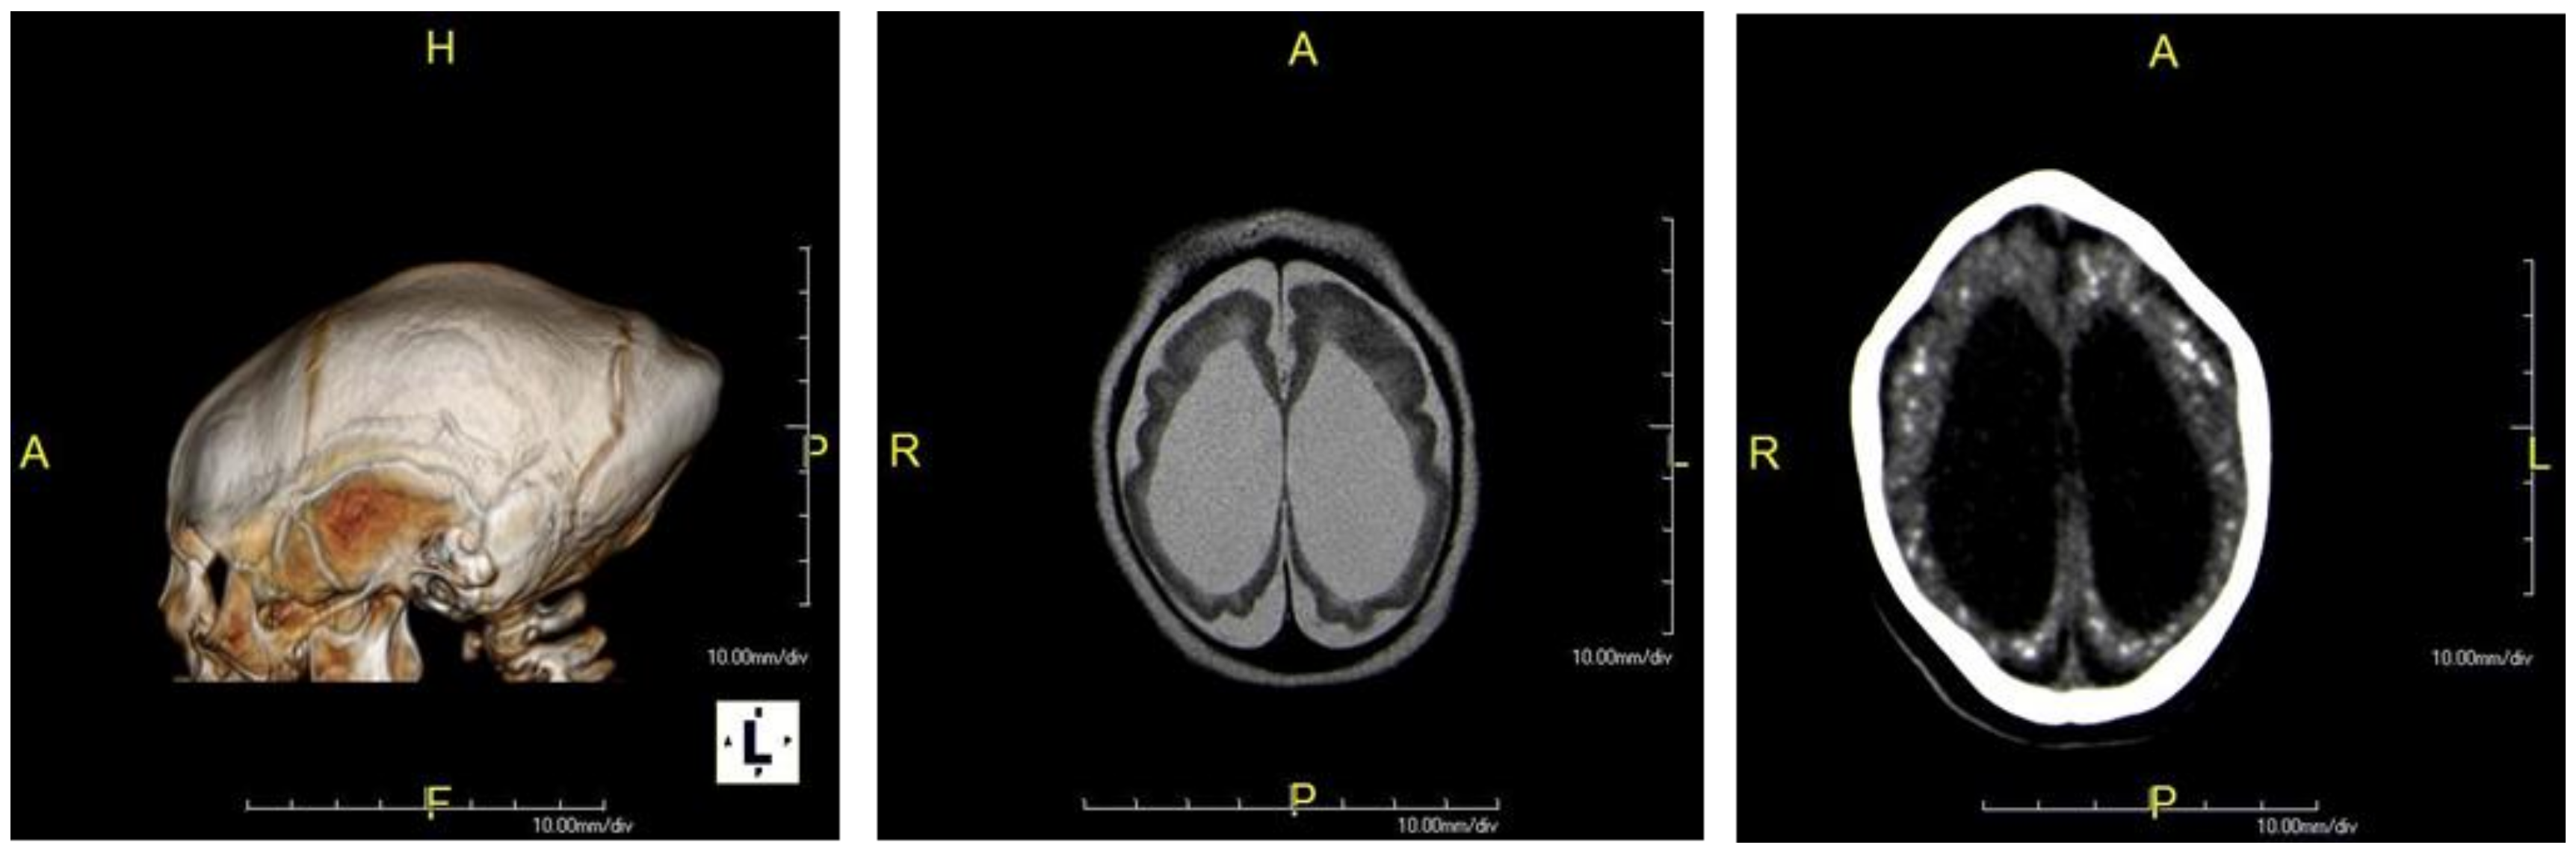

| Neuroimaging * | ||

| Cerebral atrophy | 102 | 94 (92.1) |

| Ventriculomegaly | 101 | 93 (92.1) |

| Malformation of cortical development | 101 | 86 (85.1) |

| Location of calcifications | ||

| • Cortical and subcortical | 101 | 81(80.2) |

| • Basal ganglia | 101 | 62 (61.4) |

| • Periventricular | 101 | 30 (29.7) |

| • Brainstem | 101 | 10 (9.9) |

| • Cerebellum | 101 | 3 (2.9) |

| Corpus callosum abnormalities | 102 | 76 (74.6) |

| Enlarged subarachnoid space | 101 | 51 (50.5) |

| Cerebellum hypoplasia | 101 | 24(23.7) |

| Brainstem hypoplasia | 101 | 20 (19.8) |

| Enlarged cisterna magna | 101 | 19 (18.8) |

| Delayed myelination | 97 | 5 (5.1) |

| Intraparenchymal cysts | 101 | 2 (1.9) |